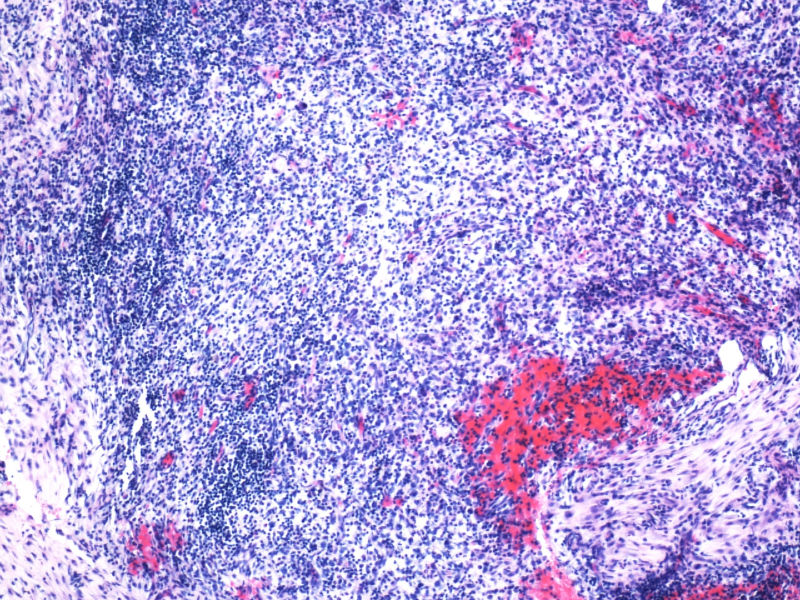

1. 支持CHL的方面: 本例CD15和D30,尤其是前者的表达强烈支持霍奇金淋巴瘤CHL,但似乎也不能完全排除ALCL;EMA-也支持CHL;

2. 支持ALCL的方面: 但CHL一般有更好的PAX5-表达;CHL的CD68一般不表达,而ALCL的KP1可以+但PGM1多-;CD3+细胞不多,可能是肿瘤细胞缺失了CD3的表达,如果再有CD5,CD4的结果就更好了;

3. 其他标记:如ALK, EBER, Oct-2, Bob-1, CD4,KP1,PGM1, ganzymeB, MUM1等对诊断也有帮助,另外也需考虑其他疾病。

本例全B,全T缺失,使诊断很困难,淋巴瘤范围内一般考虑①HL;②浆细胞分化的肿瘤如浆细胞骨髓瘤或浆母细胞瘤;③ALCL. 以下为鉴别:

1.关于CD15:可见于HL,偶尔(WHO: rarely)见于ALCL,甚至可意外地或异常地(WHO: exceptionally)见于外周T,非特指.

2.关于PAX5:应该是HL和ALCL鉴别非常好的标记。WHO: The B-cell nature of HRS cell is further demonstrable in approximately 95% of cases by their expression of the B-cell specific activator protein PAX5. 本例PAX5阴性,重点就只有放在ALCL上了。

3.关于CD43: 对比CD43和CD3的结果,并不能否认ALCL,甚至还提供了一个线索就是CD3- 是由于肿瘤细胞“改头换面”缺失表达造成的,如果追加CD2,4,5等可能就会使肿瘤“原形毕露”了。

最后,ALK+可证实以上的推断。